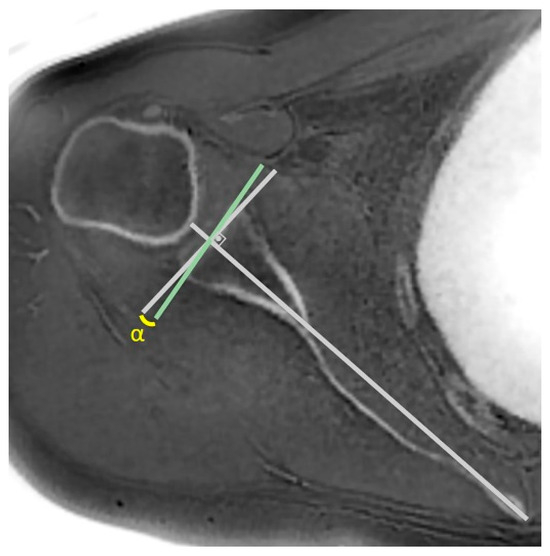

Background/Objectives: Evaluating glenoid changes in rotator cuff tear arthropathy (RCTA) is crucial for preoperative planning. MRI with zero echo time (ZTE) sequence, which produces CT-like images, allows for the assessment of osseous morphology as well as factors contributing to pseudoparesis in RCTA patients. [...] Read more.

Background/Objectives: Evaluating glenoid changes in rotator cuff tear arthropathy (RCTA) is crucial for preoperative planning. MRI with zero echo time (ZTE) sequence, which produces CT-like images, allows for the assessment of osseous morphology as well as factors contributing to pseudoparesis in RCTA patients. Methods: In this retrospective study, using 3T MRI, glenoid version, glenoid vault depth, humeral subluxation index, humeral head medialization, critical shoulder angle, glenoid best-fit circle width, glenoid best-fit circle bone loss ratio (GBLR), and anterior, central, and posterior glenoid bone loss were measured on reformatted 3D ZTE images in 43 shoulders independently by three observers. The same measurements were repeated by one observer after 10 days. Muscle cross-sectional areas were measured. Patients’ active ROMs, American Shoulder and Elbow Surgeons (ASES), and Constant–Murley scores were recorded. Patients unable to perform 90° forward elevation were classified as the pseudoparesis group. Results: Interobserver agreements were good to excellent, except for glenoid vault depth, anterior bone loss, and GBLR. Intraobserver agreements were good to excellent. The pseudoparesis group showed significantly less subscapularis muscle cross-sectional area (p = 0.006). Moderate correlations were found between subscapularis cross-sectional area and forward elevation, abduction, and internal rotation ([r = 0.471, p = 0.001]; [r = 0.447, p = 0.003]; [r = 0.464, p = 0.002], respectively). Moderate negative correlations were found between anterior glenoid loss and forward elevation (r = −0.411, p = 0.006) and abduction (r = −0.475, p = 0.001). Conclusions: MRI with ZTE sequence demonstrated good reliability for assessing osseous morphology in shoulders with RCTA. Glenoid anterior bone loss and loss of subscapularis muscle are both associated with pseudoparesis. Full article

Show Figures

Figure 1